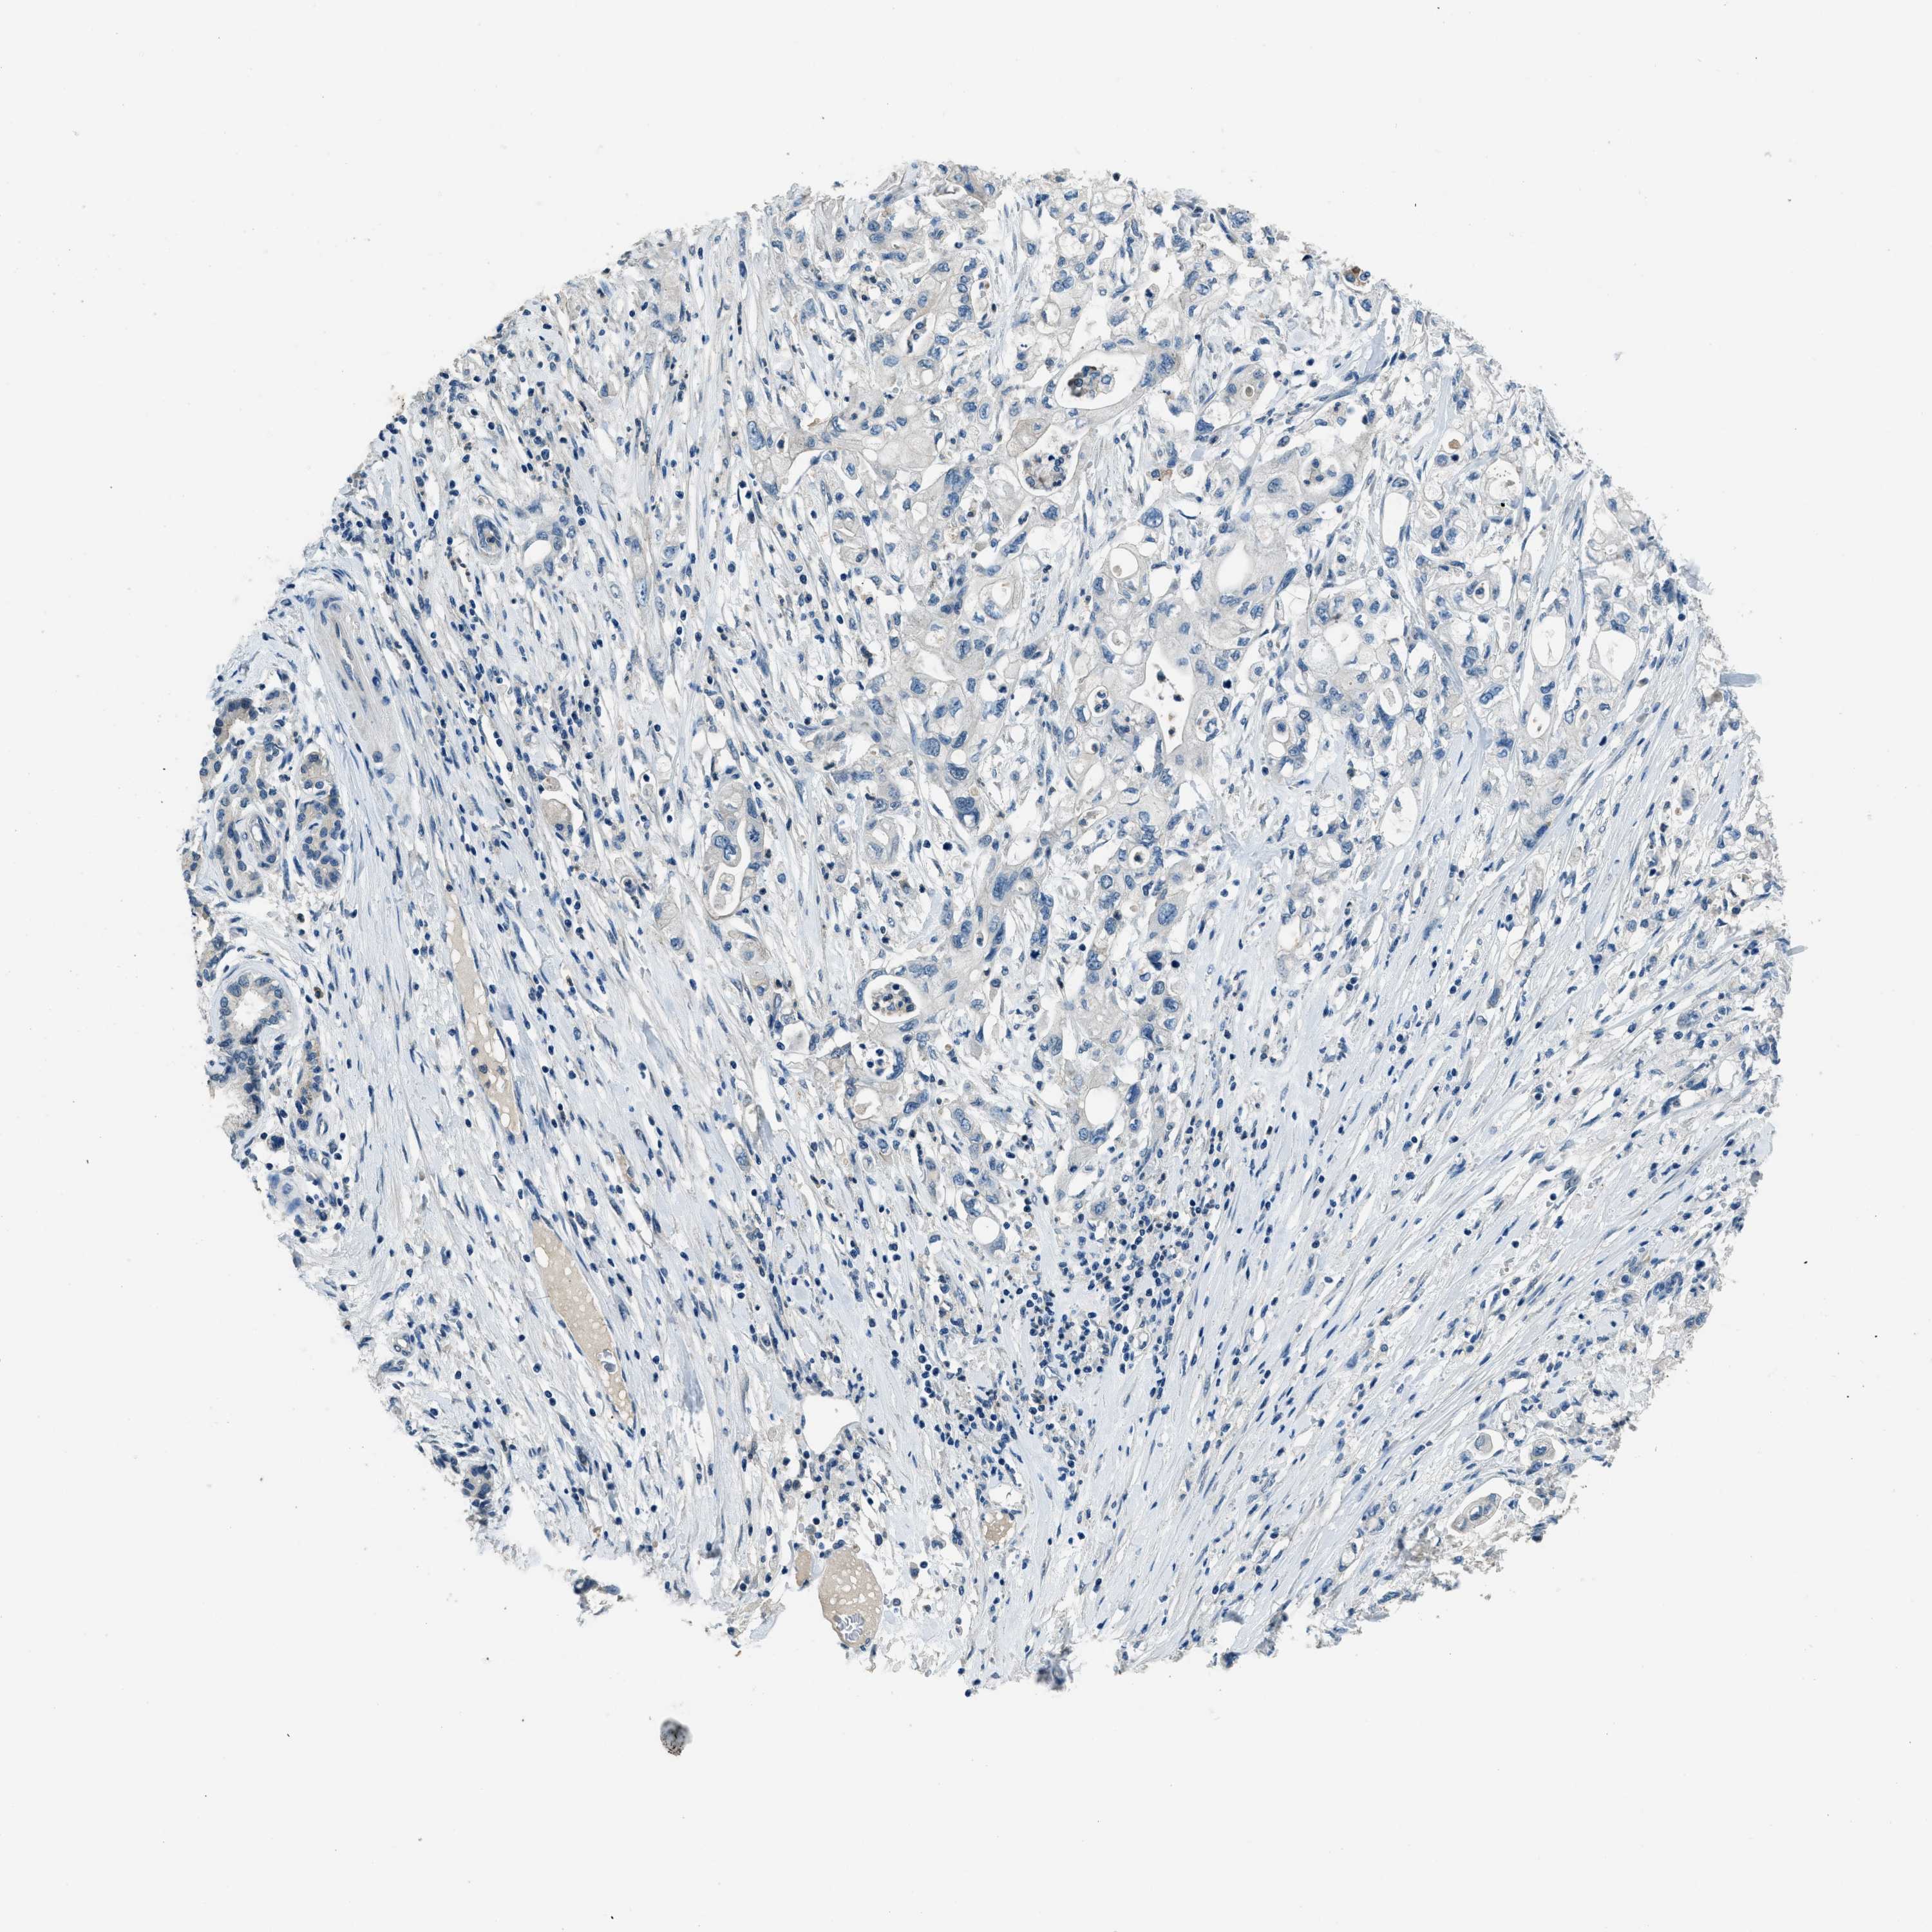

PANCREATIC CANCER - Protein expressioni

A mouse-over function shows sample information and annotation data. Click on an image to view it in a full screen mode. Samples can be filtered based on level of antibody staining by selecting one or several of the following categories: high, medium, low and not detected. The assay and annotation is described here.

Note that samples used for immunohistochemistry by the Human Protein Atlas do not correspond to samples in the TCGA dataset.

Antibody stainingi

Antibody staining in the annotated cell types in the current human tissue is reported as not detected, low, medium, or high, based on conventional immunohistochemistry profiling in selected tissues. This score is based on the combination of the staining intensity and fraction of stained cells.

Each image is clickable and will lead to virtual microscopy that enables deeper exploration of all samples and also displays staining intensity scores, fraction scores and subcellular localization as well as patient and tissue information for each sample.

Antibody HPA001818

Antibody CAB018352

Staining

High

Medium

Low

Not detected

Intensity

Strong

Moderate

Weak

Negative

Quantity

>75%

75%-25%

<25%

None

Location

Nuclear

Cytoplasmic/membranous

Cytoplasmic/membranous,nuclear

Adenocarcinoma, NOS